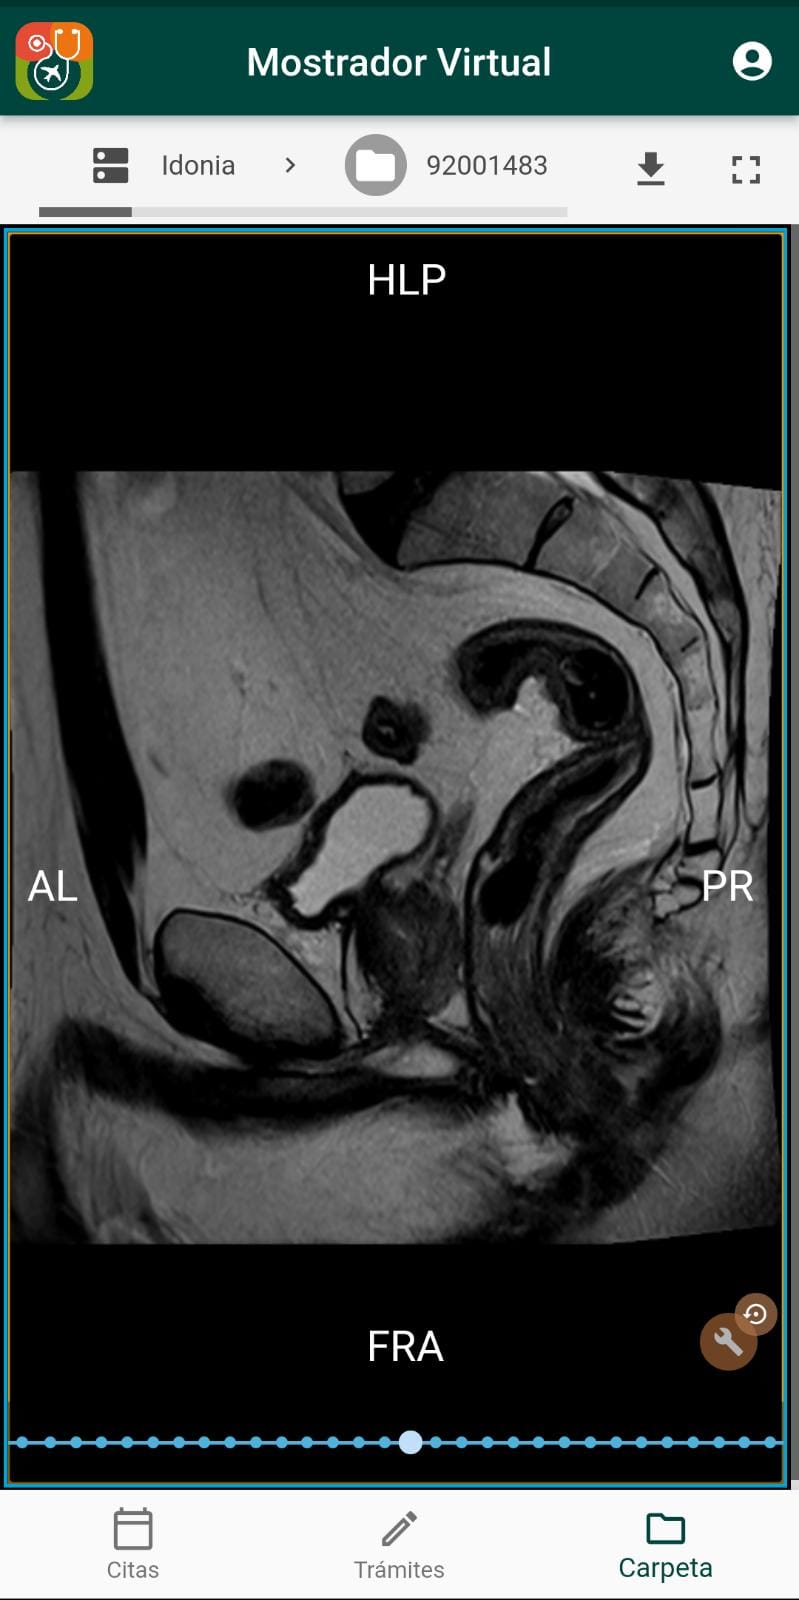

14 de junio de 2022 - 12:31Visualización y descarga de imágenes radiológicas Foto Anterior2 de 3Foto SiguienteVer el artículo original: Las nuevas funcionalidades de la App Mostrador Virtual MS del Departamento de Salud de Dénia App Mostrador Virtual MS Comprueba los resultados de tus radiografías Mostrador Virtual de Marina Salud